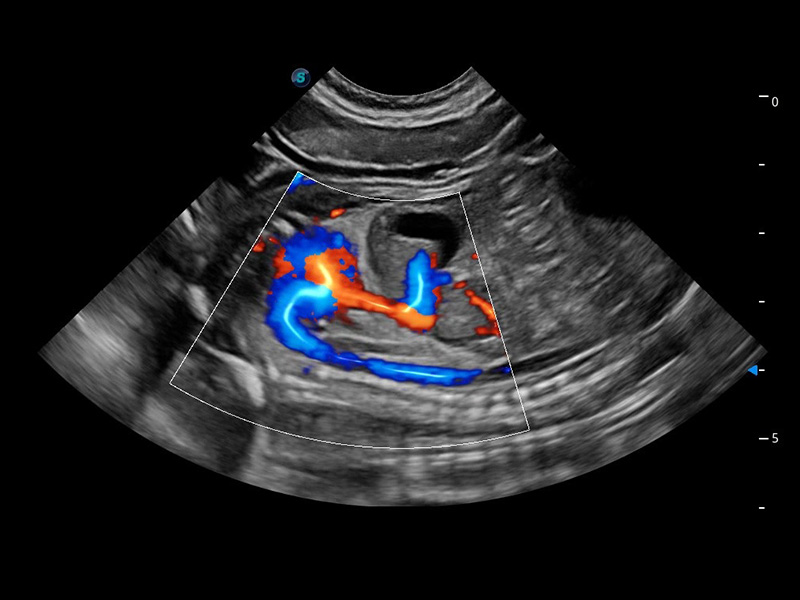

ProPet 60 作为一款高端台式动物超声设备,为动物医生的日常诊断提供了一系列贴合动物临床需求、解决临床实际问题的高级成像功能。凭借全系列高清探头,满足医生对腹部、心脏、生殖、浅表、肌骨等成像的所有需求,切实帮助您提升检查效率,提高诊断信心。

动物是人类最亲密的朋友和最值得信赖的伙伴。新葡的京集团8814检测站也一直致力于探索动物专用的超声影像解决方案。 全新推出的ProPet系列,是新葡的京集团8814检测站在动物超声影像智能化、专业化、精准化的一次跨越式革新。动物不能用言语来表述自己的不适,通过超声影像,ProPet系列搭建了动物医生与不同物种沟通的“桥梁”,为动物医生注入了“治愈之力”。